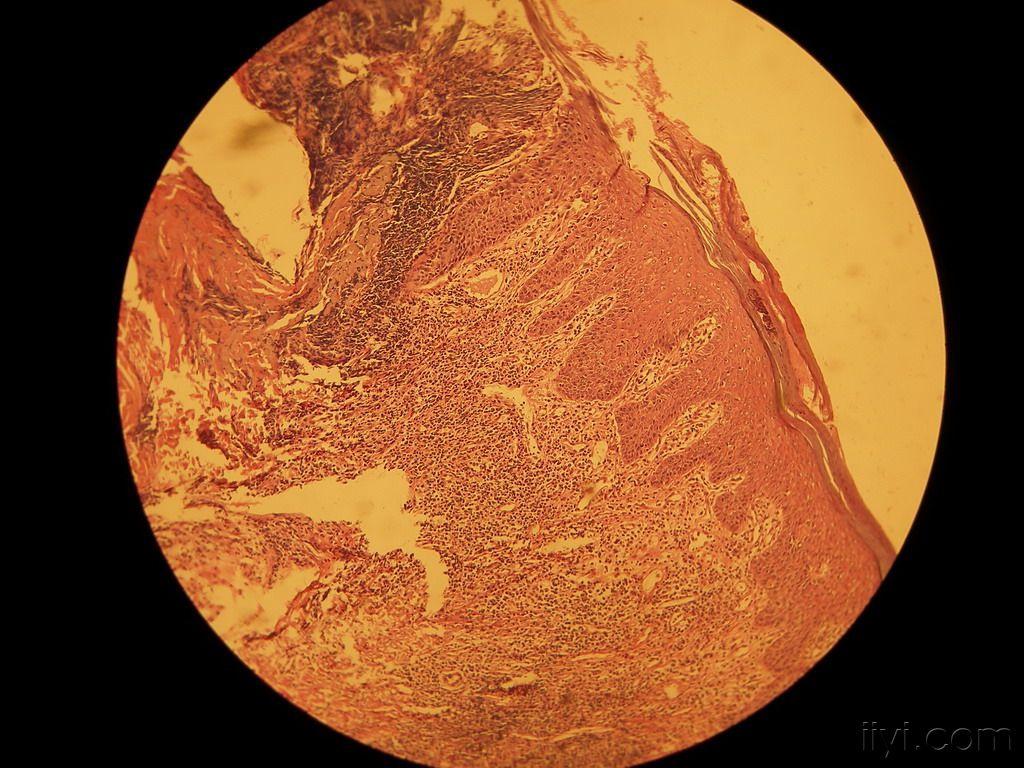

寻常型银屑病组织病理

图片尺寸1000x679